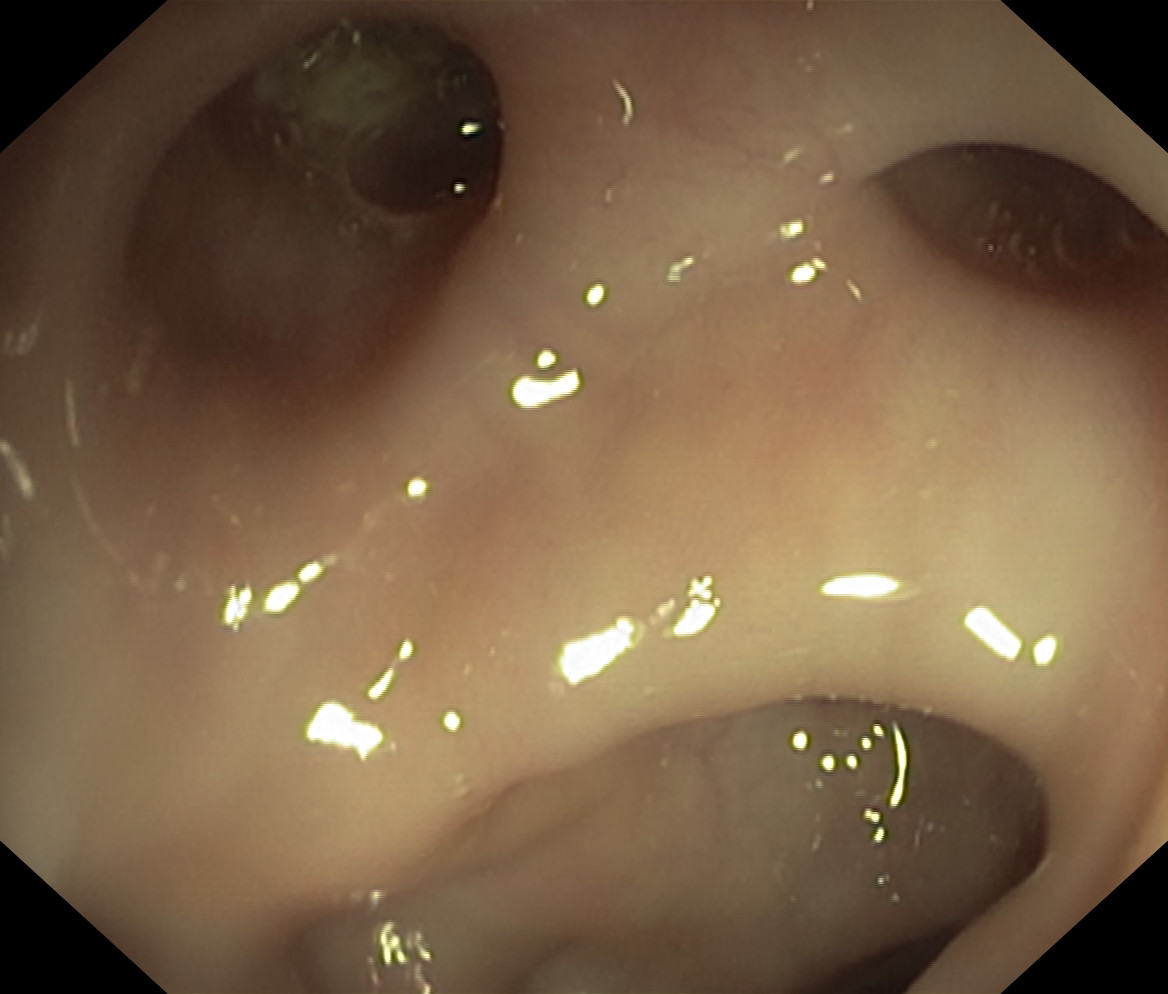

Uchyłki